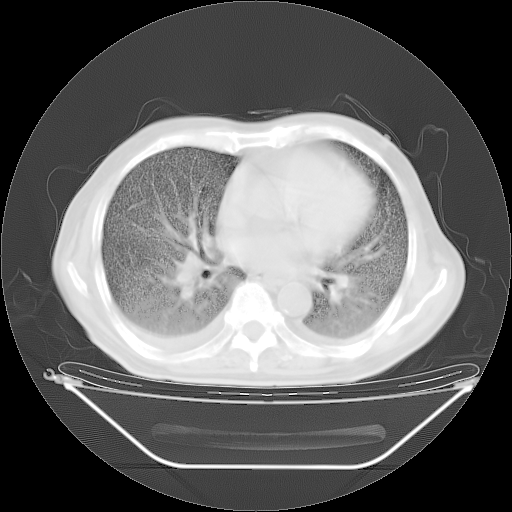

5月9日肺部CT(在4月27日齐鲁医院肺部CT描述部分肺组织磨玻璃样改变,12天后肺组织广泛磨玻璃样改变)

2009年5月9日肺部CT

大致读了系列胸部CT:纵隔窗无明显异常,肺窗:从4、27至今:主要是双肺中下野外带可见毛玻璃样改变,目前处于急性肺泡炎阶段,至于原因考虑1、结替组织或胶原血管性疾病所致?2、恶性疾病如恶组在肺部所致的表现或细支气管肺泡癌?3、药物或其它原因如肺蛋白沉着症所致肺泡炎目前不太可能?总之,明天就去请我院的呼吸科、感染科、血液科和临免专家会诊哈。